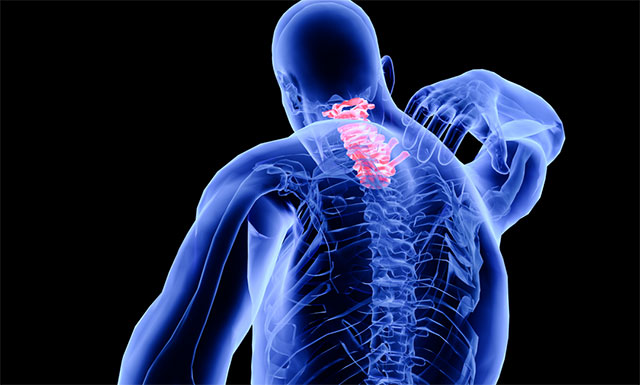

▲ 脊髓空洞症示意图

脊髓空洞症是脊髓的一种慢性、进行性的病变。其病变特点是脊髓(主要是灰质)内形成管状空腔以及胶质(非神经细胞)增生。常好发于颈部脊髓。当病变累及延髓时,则称为延髓空洞症。流行病学数据表明,该病每10万人群中约2-8人发病,多见于20-50岁,女性多于男性,是一种比较少见的疾病。

脊髓空洞症则是由于各种先天或后天因素导致产生进行性脊髓病的脊髓空穴样膨胀,临床表现为节段性、分离性感觉障碍、节段性肌肉萎缩和传导束性运动、感觉及局部营养障碍。脊髓空洞症分为交通性和非交通性两大类:交通性脊髓空洞症意指空腔与脊髓中央管相通,是一种脑脊液通路的液体动力学障碍疾病。反之,非交通性脊髓空洞症只是脊髓内的囊性扩张,不与脑脊液通路相连。